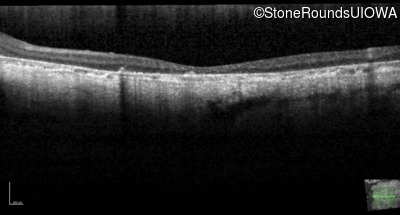

| AR Stargardt Disease | ABCA4 | Cys205Phe TGC>TTC | Gly863Ala (G)GA>(G)CA | AR |